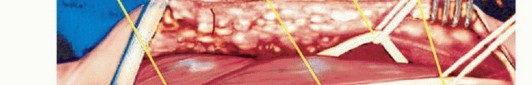

تُجرى الجراحة تحت التخدير العام وتتطلب دقة متناهية.

وضعية المريض والشق الجراحي

- وضعية المريض: يوضع المريض مستلقيًا مع إبعاد الذراع المصابة ووضعها على مسند مبطن ومعقم.

- الشق الجراحي (S-shaped incision): يبدأ الشق عادة في منتصف الذراع على طول الجانب الأنسي للعضلة ذات الرأسين، ويمتد نزولًا إلى ثنية الكوع، ثم ينحني جانبيًا على طول الجانب الأمامي للكوع. يتم تضم